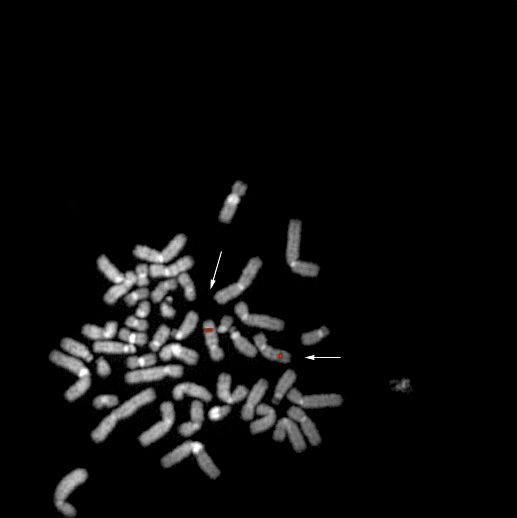

bA964D5